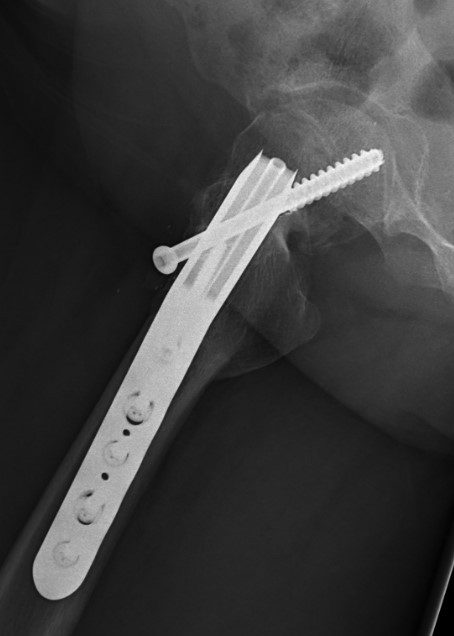

Fixation failure

Base of neck / Kramer

Technique

Closing wedge anterior and superior